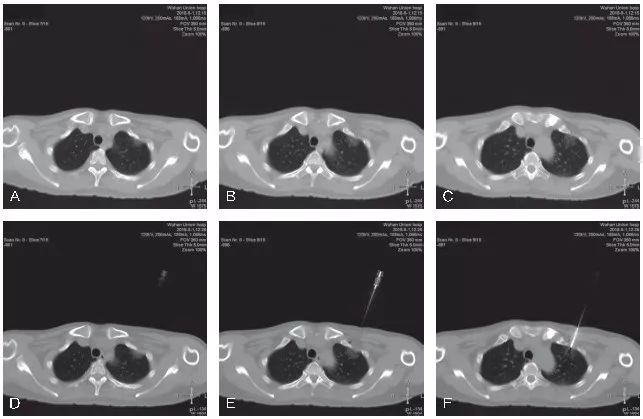

不良事件的发生率在可接受范围内。气胸是经胸廓细针穿刺活检最常见的并发症,发生率为16.0%~51.8%。在341位患者中,只有7位患者需要留置胸腔引流管。咯血发生率为8%~23%,没有患者需要治疗。从穿刺技术层面上来看,GGO的穿刺活检与普通肺结节的穿刺活检基本类似,同样需要注意避免引起气胸或出血的危险因素,从总体诊断效能及并发症发生情况来看,与普通肺结节大体一致。但也有部分研究者认为,GGO本身为经皮肺穿刺活检发生出血的一个危险因素,分析其可能的原因主要是GGO的体积通常较小,在使用全自动活检枪进行切割式活检时会损伤到更多的肺组织及肺内血管,造成较为明显的肺内出血。我院完成的GGO穿刺活检同样表现为较为明显和广泛的肺内出血征象(图5-2~图5-4)。这一点在小结节的穿刺活检中同样经常出现。因此,我们要求对于小结节/GGO的穿刺活检,务求“一击必中”。因活检取材易出现较明显的肺内出血征象,如取材不满意,即使再次进行CT扫描,亦可能无法为我们提供有效的影像引导,导致最终无法进行有效的调整,导致活检取材失败。

图5-2 A~C. 显示患者右肺下叶后基底段mGGO,选取俯卧位进行穿刺活检;D~F. 显示穿刺活检的实时CT影像,选取最短的穿刺路径,并尽量使同轴穿刺针与较粗大的肺内血管平行。图中显示同轴穿刺针到达预设位置,并未紧邻靶结节表面,为活检预留好空间,以免损伤该结节远端的肺内血管;G~I. 显示完成活检后,拔除同轴穿刺针。再次进行CT扫描,见靶结节活检区域明显的肺内渗出性改变,提示较严重的肺内出血。病理结果示:(右肺)浸润性腺癌